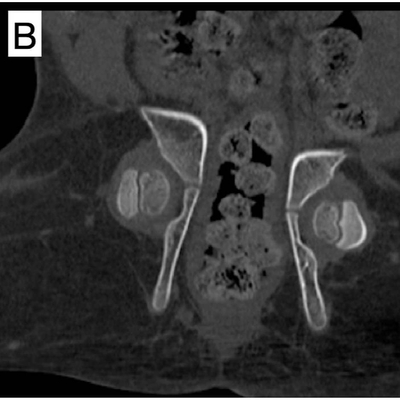

Click on an image below to view more info.